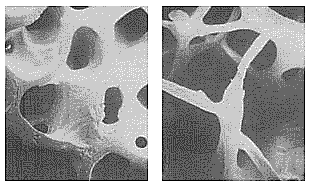

В периоде достижения пиковой массы костной ткани процессы формирования преобладают над процессами резорбции. Потеря костной массы в менопаузе сопровождается в первую очередь поражением костей с преобладанием губчатого вещества (тела позвонков, дистальные отделы костей предплечья и пр. (Рис.15). Сенильный остеопороз развивается после 70 лет и характеризуется преимущественным поражением трубчатых костей с учащением переломов шейки бедра. При одинаковом темпе потери костной ткани степень выраженности ее дефицита у женщин пожилого возраста в первую очередь зависит от величины пиковой ее массы. Дефицит половых гормонов в климактерии может оказывать и прямое, и опосредованное влияние на состояние костной ткани.

Рис. 15. Постменопаузальный остеопороз